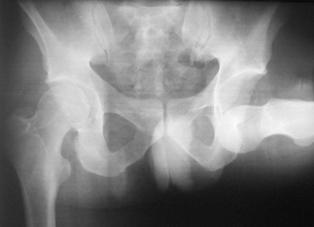

Fractura Malgaigne Fractura Malgaigne. Imagine CT

Fractura de

aripa iliaca stanga Fractura de aripa iliaca

stanga